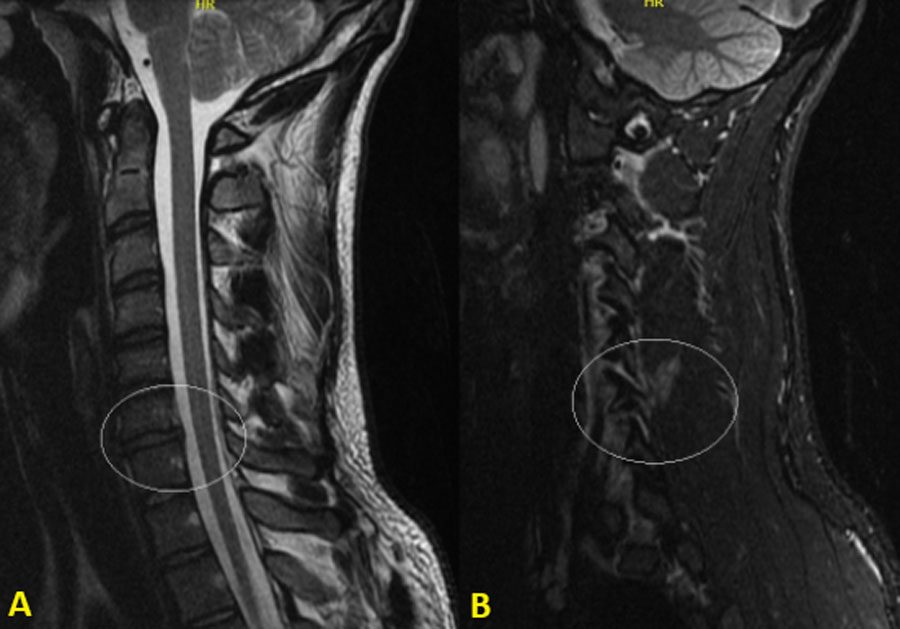

MRI showed significant edema of the left lamina and pedicle of C6, with increased joint effusion at the C6–C7 facet joint, anterolisthesis, a traumatic posterior disc protrusion (left-extruded) compressing the anterior dural margin, and inflammatory changes in paravertebral muscles. There was also facet fluid, subtle misalignment at C5–C6, and a high STIR signal in interspinous ligaments from C4 to C7. The spinal cord was intact, with there is no canal compromise.

Diagnosis: AO-F3 fracture of the left facet joint at C6–C7 with occult instability, confirmed by MRI.